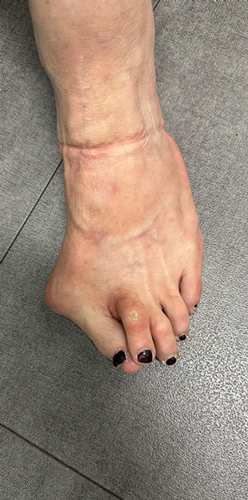

TOTAL ANKLE REPLACEMENT :: ORIF CALCANEUS :: ORIF ANKLE FRACTURE DISLOCATION :: COMPLEX BUNION AND LESSER TOE CORRECTION :: TALUS FRACTURE -1 :: TALUS FRACTURE -2 :: LISFRANC REPAIR :: COMPLEX TRIPLE ARTHRODESIS 1 :: COMPLEX TRIPLE ARTHRODESIS 2 :: MINIMALLY INVASIVE BUNION REPAIR 1 :: MINIMALLY INVASIVE BUNION REPAIR 2 :: ARTHROSCOPIC CARTILAGE REPAIR :: TENEX SPUR DEBRIDEMENT :: Haglunds Debridement and Achilles Repair